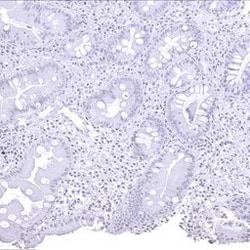

Helicobacter pylori are spiral-curved, gram-negative bacteria that is present on surface epithelium of the mucous layer of the stomach. Immunohistochemical techniques using a Helicobacter pylori antibody can distinguish it from other types of curved bacteria.There is evidence showing that these bacteria may play a significant role in peptic ulcer disease. A study has suggested that Helicobacter pylori infection is a risk factor for colorectal polyps in children. The small spiral-curved shaped bacterium can be seen clearly using a 100X oil objective under the microscope.z

Newcomer Supply Helicobacter sp. Control Slides are for the positive histochemical staining of Helicobacter sp., a spiral shaped bacterium associated with stomach inflammation and implicated in the development of gastric malignancy, peptic ulcers, and chronic gastritis. Helicobacter sp. Control Slides contain sections of positive staining gastrointestinal tract.